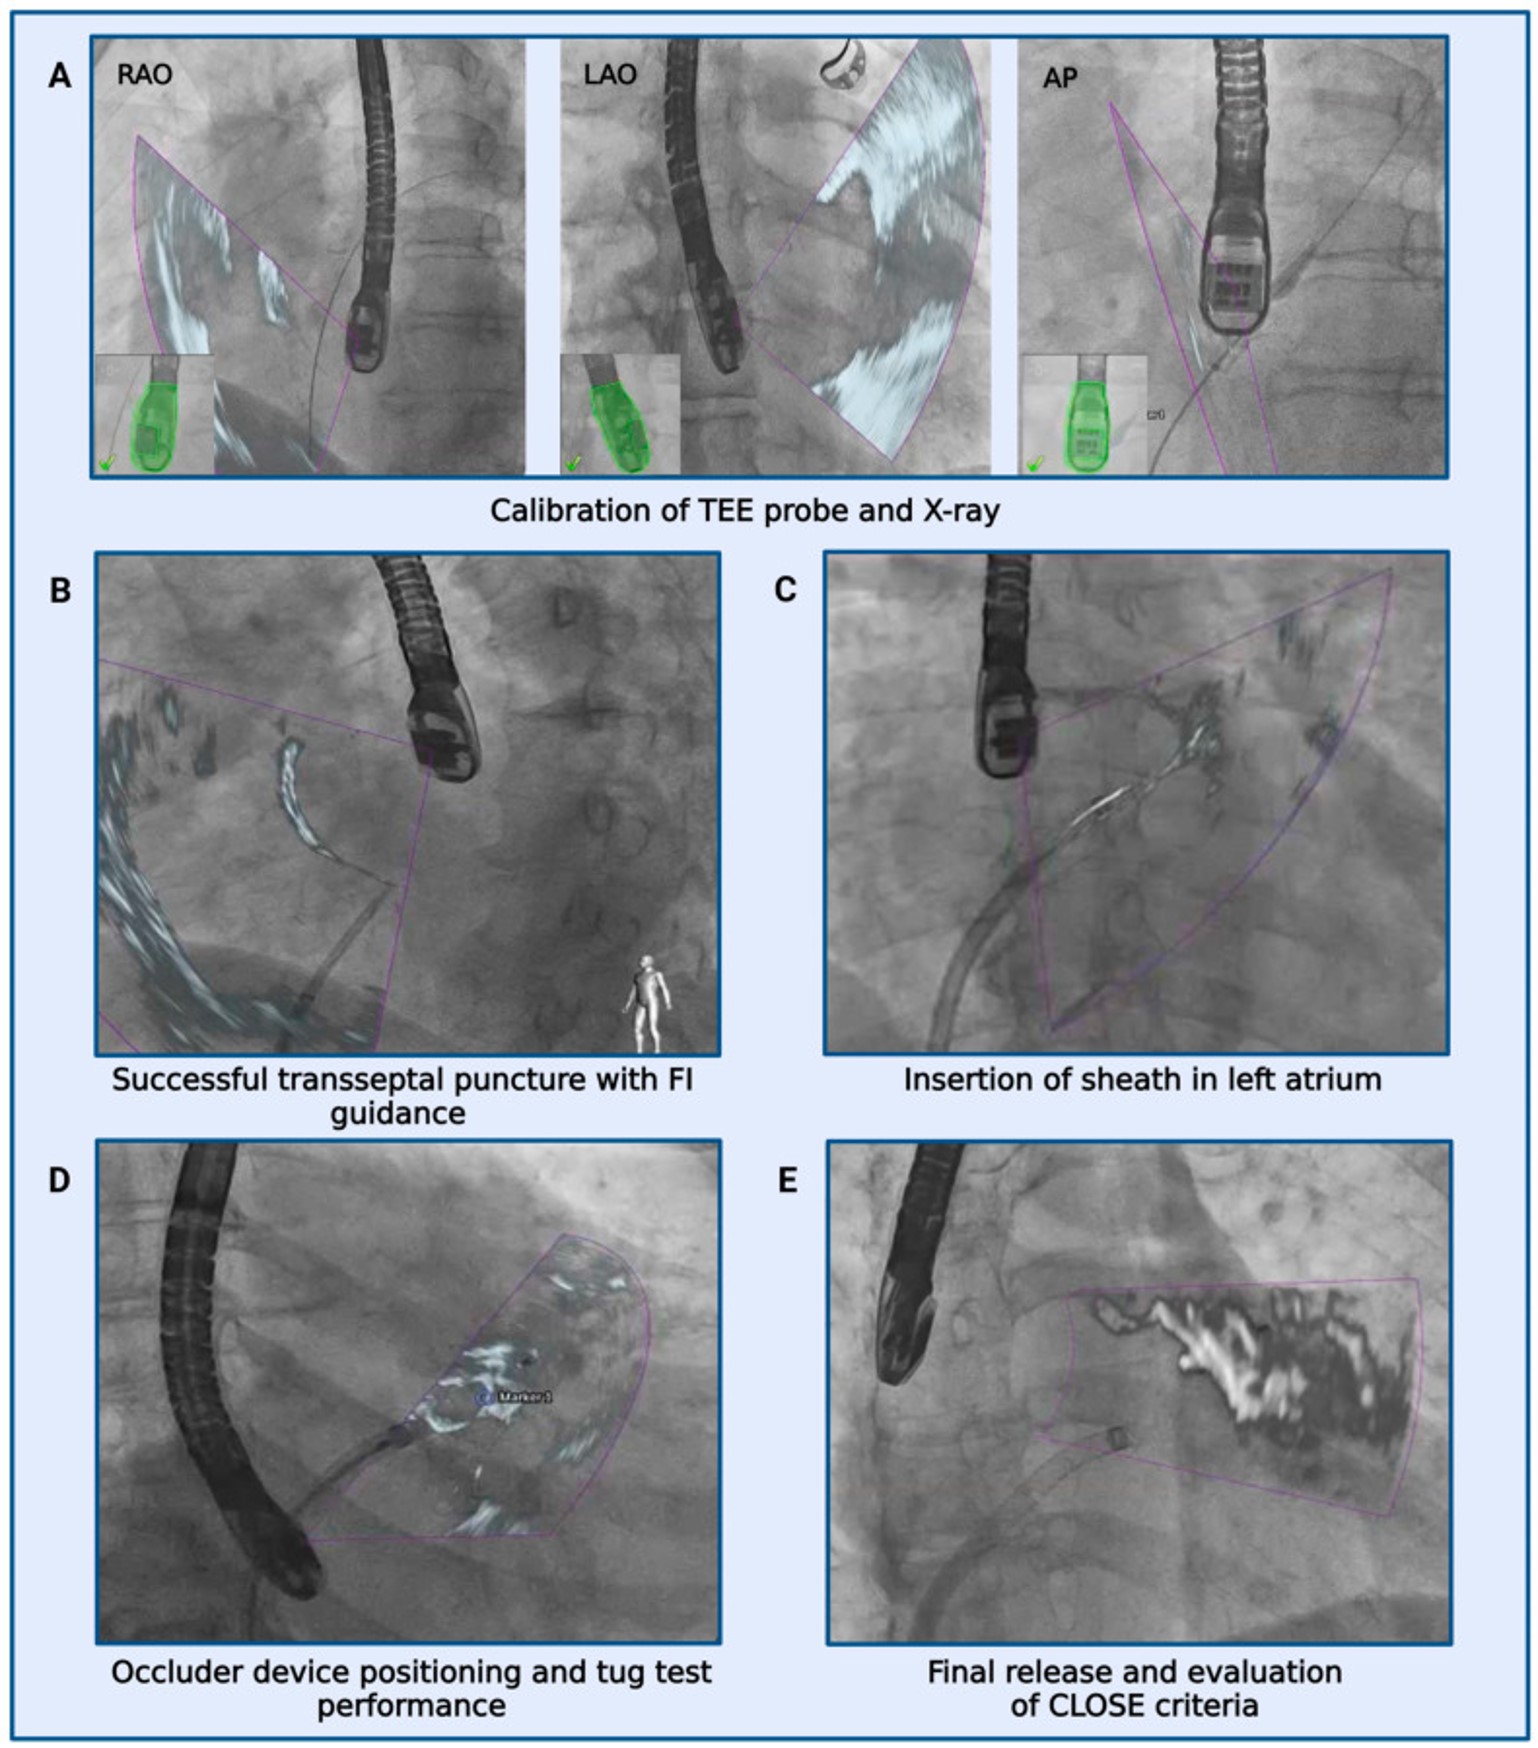

Structural heart disease is the fastest growing subspeciality in cardiology. Interventional success is highly dependant on pre- and periprocedural imaging. The working group is concentrating on the evaluation of the clinical benefit through these novel modalities.